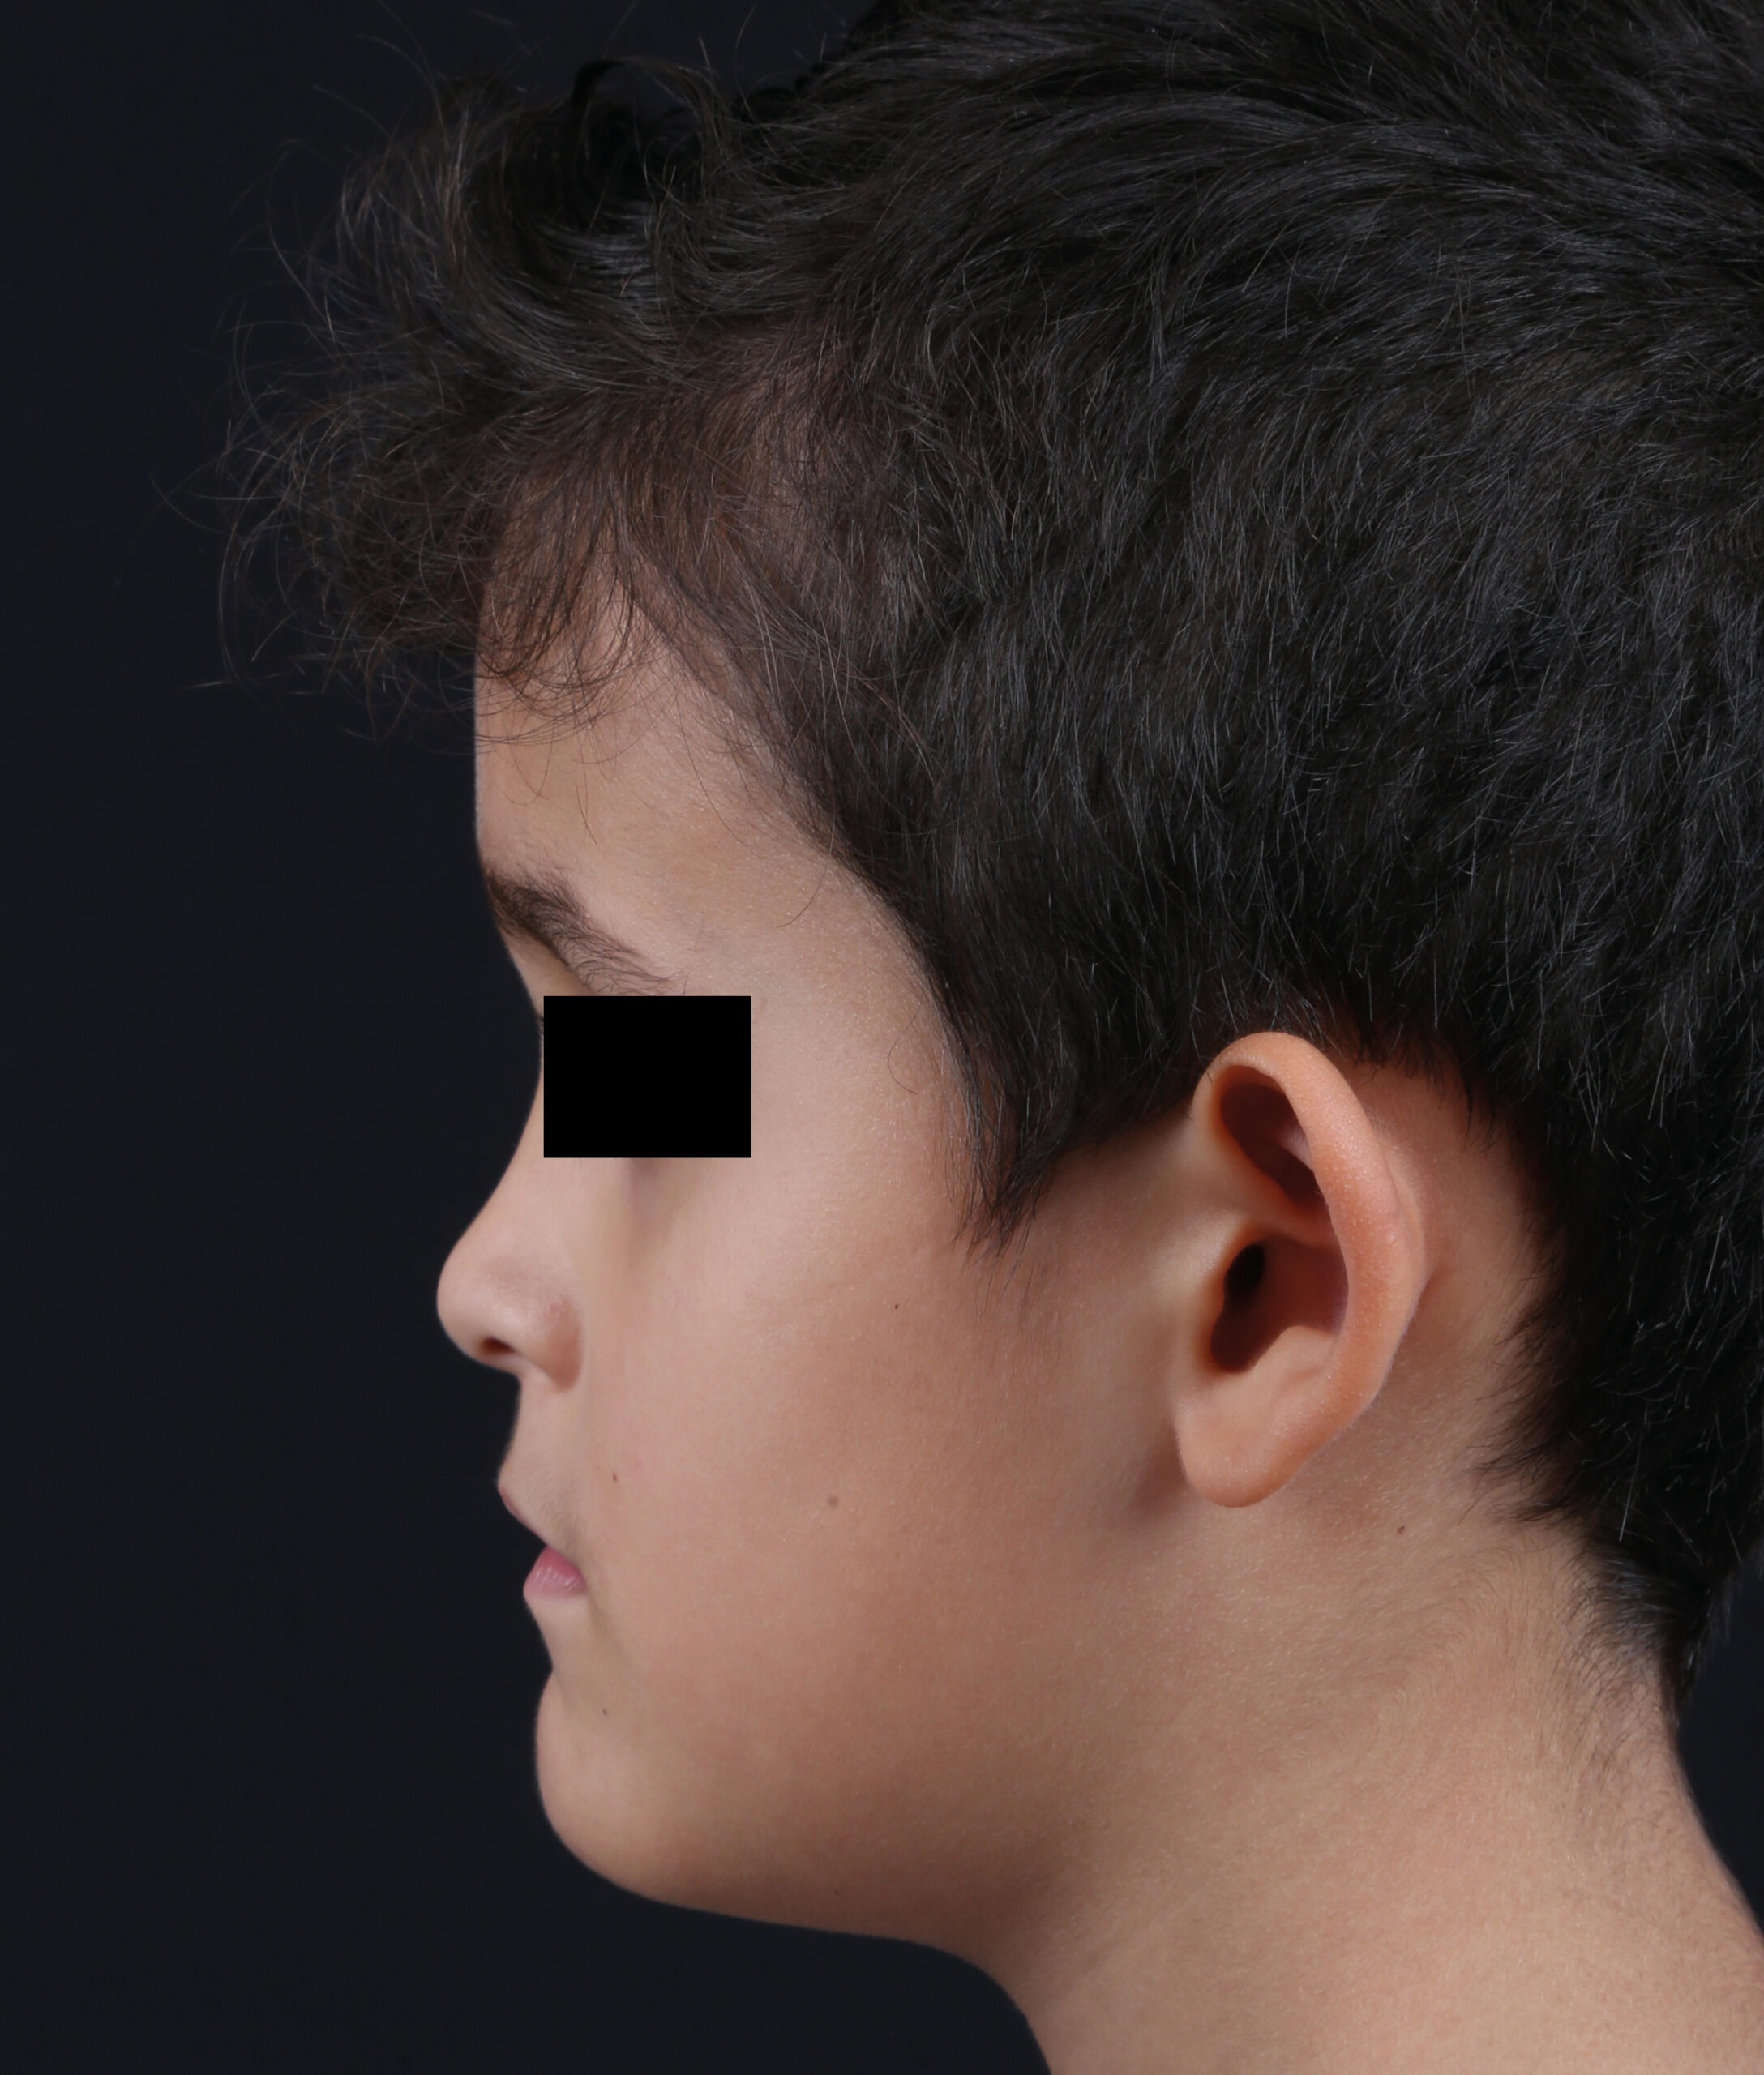

Fotografía Médica odontológica intra y extraoral

Registro fotográfico que se toma antes y después de los tratamientos odontológicos. sirve para evaluar y captar los rasgos intraorales y las características faciales.

Estas imágenes se emplean al iniciar el tratamiento mostrando el estado actual de la boca del paciente, se utilizan también para llevar un seguimiento y comparar luego del tratamiento para mostrar los resultados obtenidos.